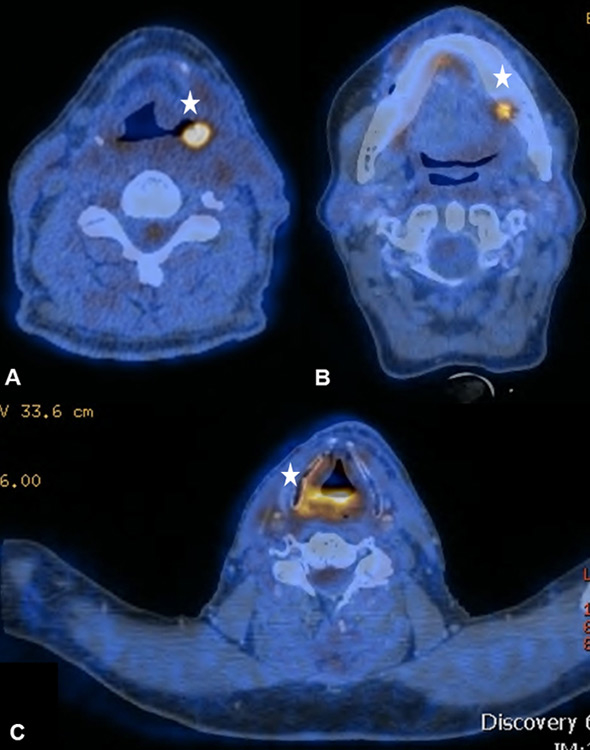

Figure 7

(A) Sixty-two year old patient after curative radio-chemotherapy (RCT) for a supraglottic larynx carcinoma with increased focal uptake in the left hypopharynx due to a radiogenic ulcer. (B) Increased focal uptake of the left mandible due to osteoradionecrosis in a 48-year old patient after curative RCT for an oropharynx carcinoma (C) Radiogenic chondronecrosis of the corniculate cartilages in a 59-year old patient after surgical resection and radiation therapy of a base of tongue carcinoma

Irradiation-related inflammatory FDG uptake was observed because of a radiogenic ulcer in the hypopharynx, osteoradionecrosis, radiogenic chondronecrosis and chronic mucosal inflammation (fig. 7ABC). The occurrence of false-positive FDG uptake caused by osteoradionecrosis in HNC patients after RT is a known difficulty and well-reported for nasopharyngeal carcinoma [34, 35]. Management of these lesions is challenging since the clinical examination can be inconclusive and definitive exclusion of malignancy often requires multiple biopsies. Re-evaluation by a multidisciplinary tumour board plays a pivotal role in adequate management of these challenging patients: surgeons, nuclear medicine physicians, radiation oncologists, oncologists and pathologists need to carefully review indistinct findings and to determine individual diagnostic algorithms.